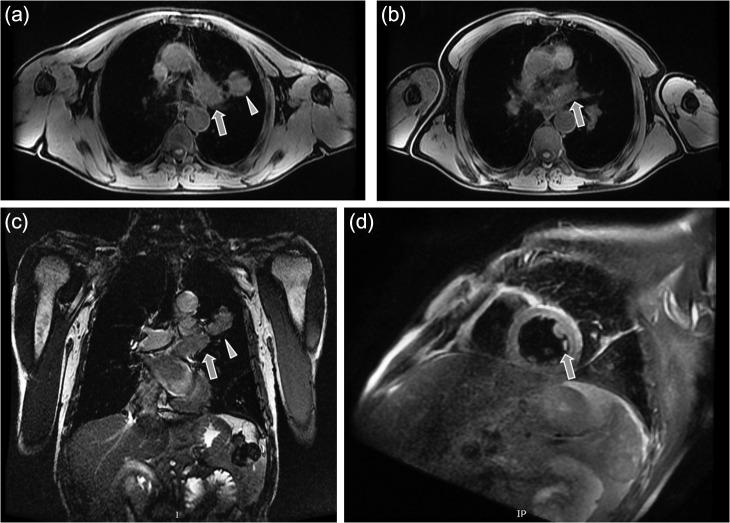

A 61-year-old man presented with dyspnea, left thoracic pain and productive cough. Chest computed tomography demonstrated a solid mass of the left upper lobe, 2.9 × 1.8 cm in size, which had irregular borders and appeared to infiltrate and totally occlude the upper left pulmonary vein extending up to the left atrium (LA) with thrombus formation. The patient underwent median sternotomy and left pneumonectomy, combined with LA thrombus resection under cardiopulmonary bypass (CPB) with bicaval cannulation. The LA was partially resected and the intracavitary thrombus was completely removed. The surgical margins were free of tumor cells. Episodes of embolism were not observed during surgery. The patient was successfully weaned from CPB. The postoperative course was uncomplicated. Pathological examination of the resected specimen revealed giant cell carcinoma.

一名61岁男性患者出现呼吸困难、左胸痛和咳痰。胸部计算机断层扫描显示左肺上叶有一个实性肿块,大小为2.9×1.8厘米,边界不规则,似乎浸润并完全阻塞了左上肺静脉,血栓形成一直延伸至左心房(LA)。患者接受了正中胸骨切开术和左肺切除术,并在体外循环(CPB)双腔插管下联合进行左心房血栓切除术。左心房部分切除,腔内血栓完全清除。手术切缘无肿瘤细胞。手术期间未观察到栓塞事件。患者成功脱离体外循环。术后过程无并发症。切除标本的病理检查显示为巨细胞癌。